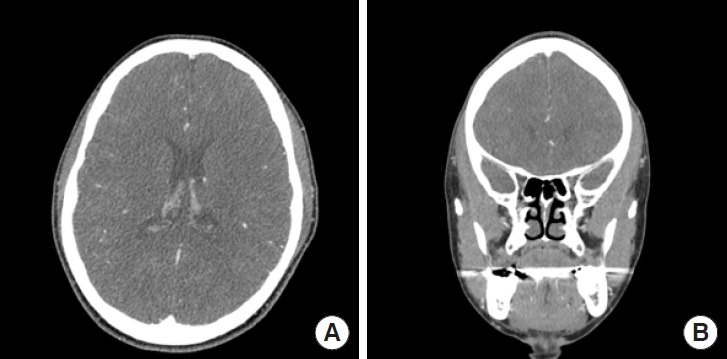

The initial instance of isolated unilateral temporalis muscle hypertrophy (IUTMH) was reported in 1990. Since then, only few cases have been documented. The cause of this condition remains ambiguous; however, it is presumed to be linked to compensatory and stress-induced hypertrophy. We introduce a rare case of the diagnosis and treatment of IUTMH. A 39-year-old woman presented with a steadily enlarging pain-free swelling on the left side of her face, first noticed a month ago. Apart from a hyperthyroidism medication regimen her medical history was unremarkable. She had no history of temporomandibular joint disease, bruxism, surgery, or trauma. However, she complained of having been under substantial stress lately. Contrast-enhanced magnetic resonance imaging revealed asymmetric temporalis muscle hypertrophy. The treatment plan consisted of administering type A botulinum toxin injections into left temporalis muscle, supplemented by lifestyle changes and relaxation techniques. At a follow-up visit 9 months after the injections, the muscle contour was normalized both in physical and in radiologic examinations. While further supportive evidence is needed, it can be anticipated that cosmetic treatment with botulinum toxin, rather than surgical interventions, will become the standard treatment of IUTMH.